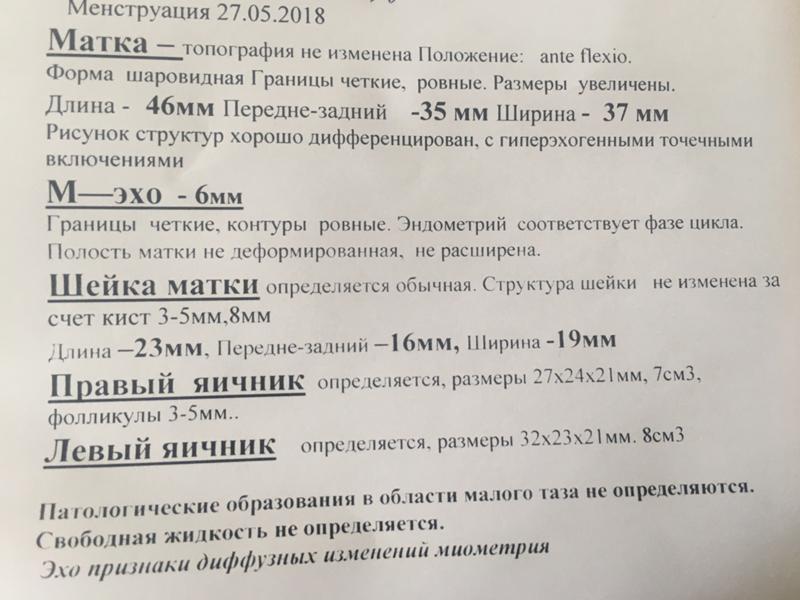

Почему разные заключения на УЗИ?